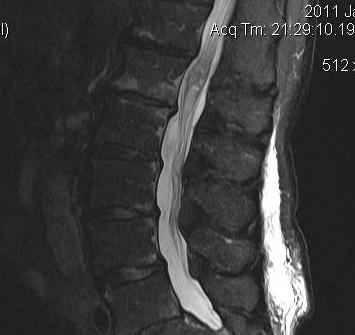

Ependymoma Conus MRI SagittalEpendymoma Conus Axial MRI